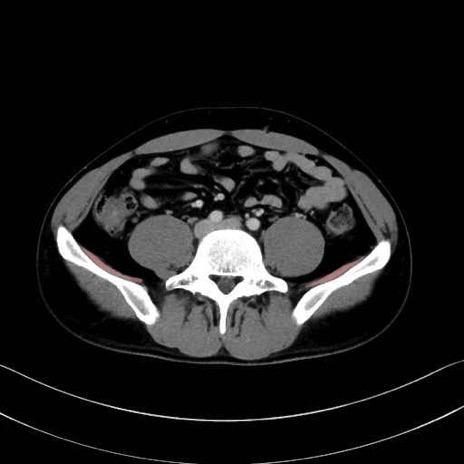

腸骨筋 (Iliacus)